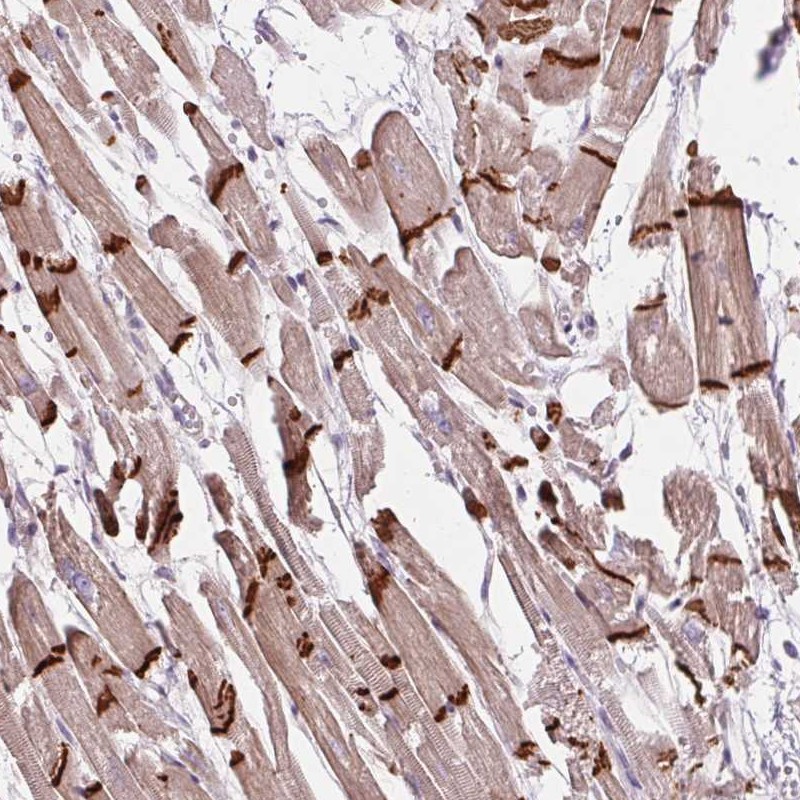

Immunohistochemistry analysis in human heart muscle and pancreas tissues using Anti-CTNNA3 antibody. Corresponding CTNNA3 RNA-seq data are presented for the same tissues.